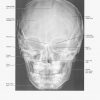

Atlas Giải Phẫu Đầu Cổ (Netter) | Bài giảng CĐHA

* Tác giả: Frank H. Netter v6 – 2016

Giải Phẫu X-Quang Sọ Mặt | Bài giảng CĐHA